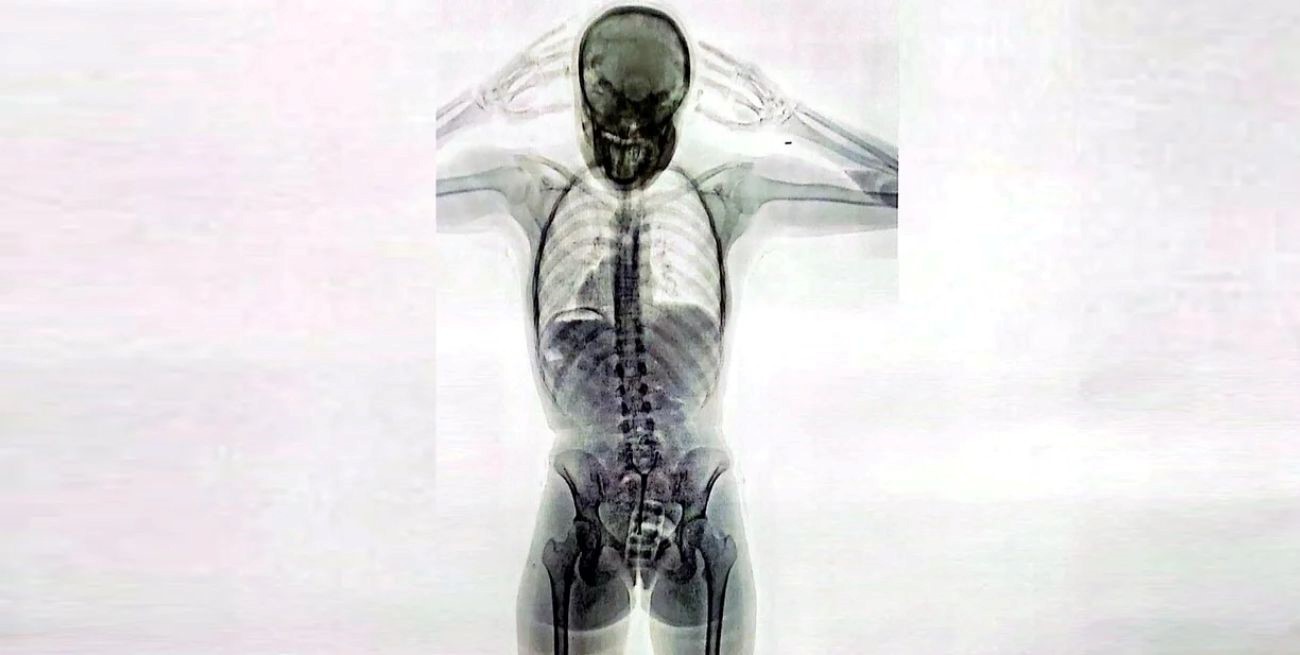

Una joven de 20 años fue detenida en los últimos días en el Aeropuerto Internacional de Ezeiza tras ser descubierta por las autoridades aeroportuarias cuando intentaba viajar a Europa con droga oculta dentro de su cuerpo. Las imágenes del escáner de rayos X revelaron la presencia de más de 700 gramos de cocaína en su vagina y su estómago.